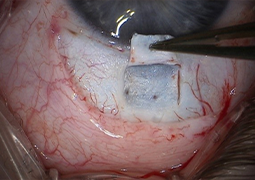

- Outcomes of Chandelier-Assisted Segmental Scleral Buckling Compared to Conventional Scleral Buckling for Primary Rhegmatogenous Retinal Detachment: A comparative retrospective study